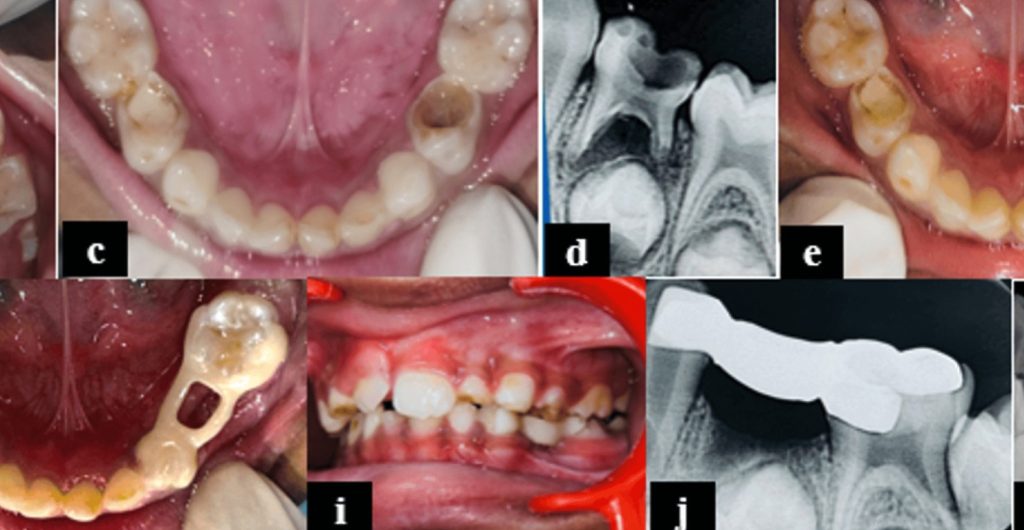

Directo del Journal of Digital Orthodontics les traemos un artículo llamado Severe Class III Malocclusion with Anterior Crossbite and Anterior Crowding: Camouflage Treatment with Premolar Extractions. Los autores nos describen el tratamiento de camuflaje de un hombre de 33 años con maloclusión Clase III esquelética severa (-4.5° ANB), apiñamiento anterior, mordida cruzada y un perfil cóncavo . Debido al rechazo del paciente a la cirugía, optaron por un enfoque ortodóntico .

El tratamiento consistió en la extracción de los segundos premolares maxilares y los primeros premolares mandibulares para generar espacio . Se utilizaron brackets de autoligado pasivos, combinados con tbite-turbos, elásticos Clase III y open coil para corregir la mordida cruzada anterior y retraer el arco mandibular.

Después de 39 meses, se logró un perfil facial y una oclusión satisfactorios . Los resultados incluyeron una mejora de 7° en la inclinación de los incisivos superiores y un mantenimiento del torque inferior, retracción mandibular de 8 mm y del labio inferior de 4 mm. ¿Como llegaron a eso? Muy fácil…